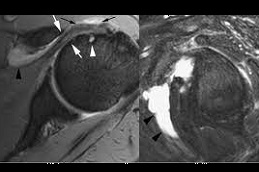

Results:

best prp-injection-for-rotator-cuff-tear in dubai prp injection for rotator cuff tear in dubai prp-injection-for-rotator-cuff-tear in Abu Dhabi